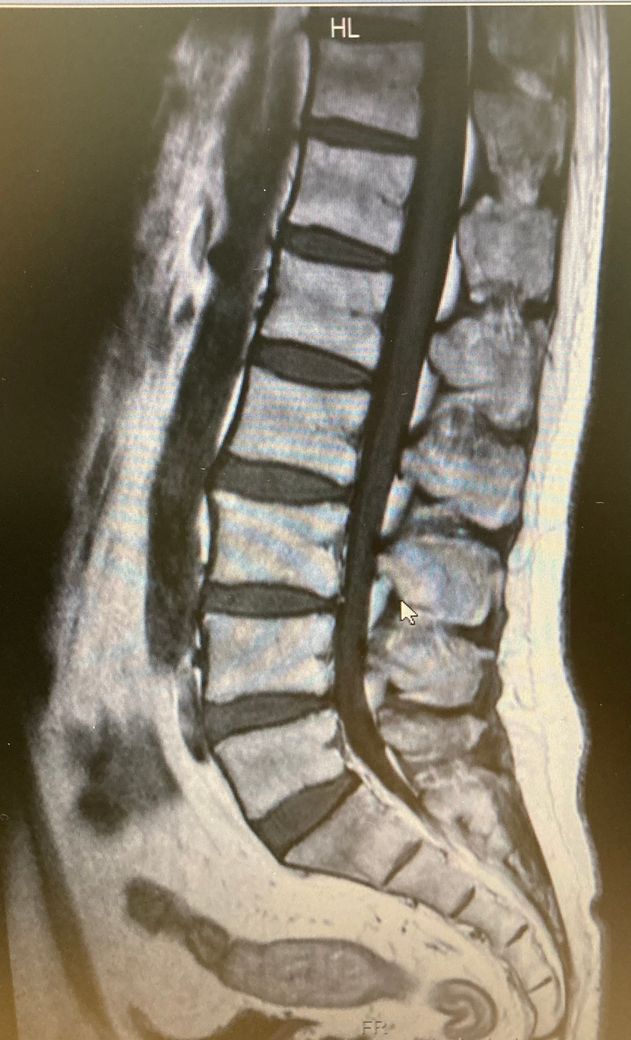

척추 X-ray 해석좀 부탁드립니다

저렇게 씨티상으로 봤을때 척추바디 사이가 파인것처럼 검은색으로 보이는 이유를 아시는 분 있을까요? 어떤 질환이 의심되는지 알려주세요

CT 촬영의 검사결과에서 검은 조직은, 일반적으로는 공기나 액체가 있는 조직을 의미하며 반대로, 척추주변의 염증이나 혈종등의 변화가 있는 경우에는 검은색으로도 보일 수 있습니다. 정상적인 척추와 비교하였을 때에 비정상적인 변화가 있는 경우 검은색으로 보일 수 있습니다. 검사결과를 들으실 때 이상소견을 듣지 않으셨다면, 크게 걱정을 하지는 않으셔도 될 것으로 생각됩니다.

척추 사이사이가 검은색으로 나오는것은 저부분은 뼈가 아니라 디스크가 들어있는 부위라 뼈와 색깔이 다르게 나오는것이 맞습니다. 저 검은부분들을 보면서 얼마나 삐져나오냐 아니냐에따라 허리디스크가 허리중에서 어느분절에있고 얼마나삐져나온지를 파악할수있는것입니다.